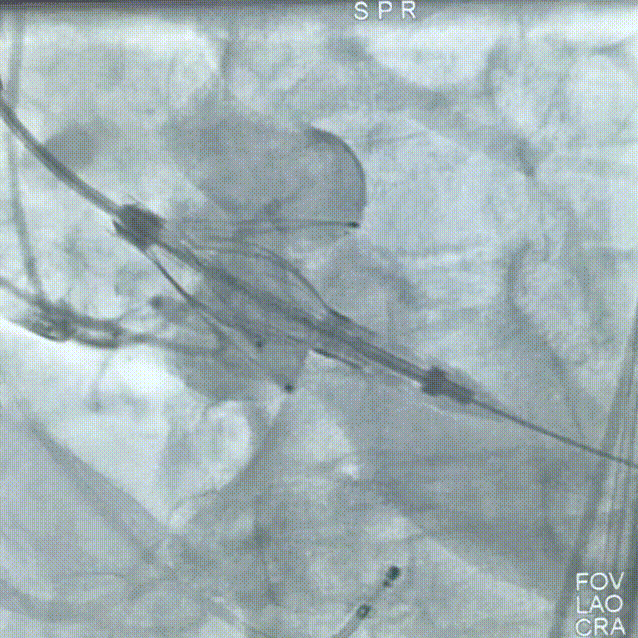

2026年伊始,TaurusTrio经导管主动脉瓣系统在复旦大学附属中山医院,浙江大学医学院附属第二医院,中国医学科学院阜外医院,首都医科大学附属北京安贞医院,四川大学华西医院等多家临床中心成功开展上市后全国首批植入。这不仅是TaurusTrio正式走向广泛临床应用的重要里程碑,更标志着中国单纯主动脉瓣反流介入治疗正式迈入了“心键合璧”的全新纪元。